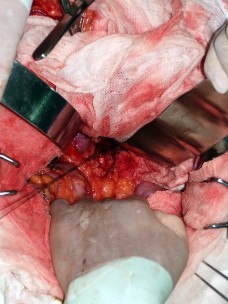

Se trata de una paciente mujer de 51 años que acudió al Hospital Loayza en marzo del 2012, con un tiempo de enfermedad de dos años, caracterizado por desvanecimiento, en especial por las noches tras la cena. No registraba antecedentes de enfermedades pancreáticas en la familia. Cuando ingresó al hospital, presentaba un cuadro de hipoglicemia de 50 mg/dl, motivo por el cual se le sometió a un dosaje de insulina, que arrojó 80 UI (rango mayor en 25 UI). Se le indicó ayuno prolongado, y se observó hipoglicemia asociada a hiperinsulinismo. El péptido C se encontraba elevado. Se decidió realizar una resonancia magnética (Figura 1), donde se evidenció una lesión nodular en la cara anterior del páncreas de aproximadamente 2 cm de diámetro. Se procedió con el dosaje de otras hormonas como cortisol y hormona tiroidea para descartar el síndrome de MEN.

Figura 1 Resonancia magnética de la paciente: lesión pancreática sugestiva de insulinoma

El caso que se presenta exhibe una clínica muy sugerente de insulinoma. Los exámenes de diagnóstico fueron acertados y se descartó la posibilidad de neoplasia endocrina múltiple. Es poco frecuente encontrar este tipo de tumores por medio de imágenes, sin embargo, en este caso se pudo identificar la neoplasia con bastante claridad (Figura 1). Esto mejora las condiciones de resecabilidad, las cuales, asociadas a maniobras quirúrgicas apropiadas como una adecuada palpación bimanual y una enucleación amplia, auguran un buen pronóstico.